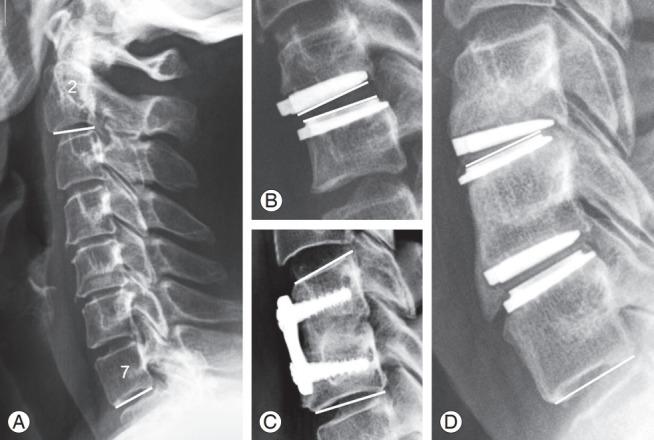

We evaluated 758 lateral cervical radiographs. One medical student and one spine surgeon (i.e., measured ×2 within 4 weeks) independently measured the parameters obtaining 5,850 values. Standard error of measurement (SEm) and minimum detectable change (MDC) were calculated for each parameter. The accuracy and reliability of the Cobb angle measurements were calculated for the different types of angles: cervical lordosis, prosthesis angle, segmental angle with two bone surfaces (SABB), and segmental angle with one bone and one metal surface. Reliability was determined with intraclass correlation coefficient (ICC).

SEm was 1.8° and MDC was 5.0° for the Cobb angle, with an intraobserver/interobserver ICC of 0.958/0.886. All the different subtypes of Cobb angles had an ICC higher than 0.950, except SABB (intraobserver/interobserver ICC of 0.922/0.716). The most accurate and reliable measurement was for KLT.

This study provides normative data on SEm and MDC for Cobb angles, T1S, KLT, OCI, and cSVA in cervical lateral radiographs. Reliability was excellent for all parameters except SABB (e.g., good).

我们评估了758张颈椎侧位X线片。一名医学生和一名脊柱外科医生(即在4周内测量×2次)独立测量这些参数,共获得5850个值。计算每个参数的测量标准误差(SEm)和最小可检测变化(MDC)。针对不同类型的角度计算Cobb角测量的准确性和可靠性:颈椎前凸角、假体角度、具有两个骨表面的节段角(SABB)以及具有一个骨表面和一个金属表面的节段角。可靠性通过组内相关系数(ICC)确定。

Cobb角的SEm为1.8°,MDC为5.0°,观察者内/观察者间ICC为0.958/0.886。除SABB外(观察者内/观察者间ICC为0.922/0.716),Cobb角的所有不同亚型的ICC均高于0.950。最准确和可靠的测量是KLT。

本研究提供了颈椎侧位X线片中Cobb角、T1S、KLT、OCI和cSVA的SEm和MDC的规范数据。除SABB外(例如,良好),所有参数的可靠性都非常好。